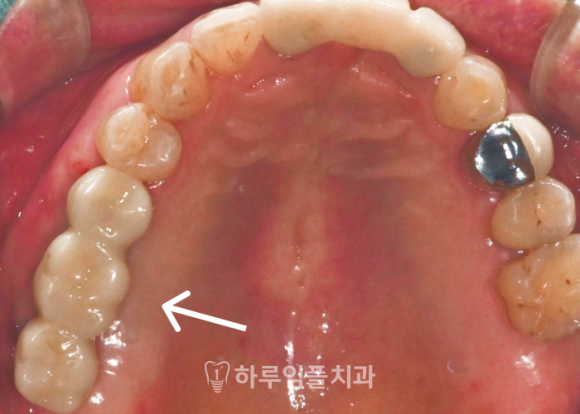

맞춤형 어버트먼트를

체결한 모습입니다.

환자 개개인의 잇몸 형태와 뼈 높이는

모두 다르기 때문에,

기성 어버트먼트를 사용하면

보철물과 잇몸 사이에

미세한 틈이나 단차가 생기기 쉽습니다.

이 틈은 시간이 지나면서

음식물 저류나

세멘트 잔여물 축적을 유발하여

염증으로 이어질 수 있습니다.

맞춤형 어버트먼트는

디지털 스캔 데이터를 기반으로

잇몸 곡선을 그대로 반영해 제작되므로,

보철물이 올라갔을 때

잇몸과 자연스럽게 이어지고

위생 관리도 수월합니다.

최종 보철물은

잇몸과 부드럽게 이어지며

깔끔하게 완성되었습니다.

어버트먼트 위에 정확히 안착되어,

음식물이 끼거나

잇몸에 무리가 가지 않도록 설계되어

오래 사용하시기 좋은

튼튼한 형태입니다.